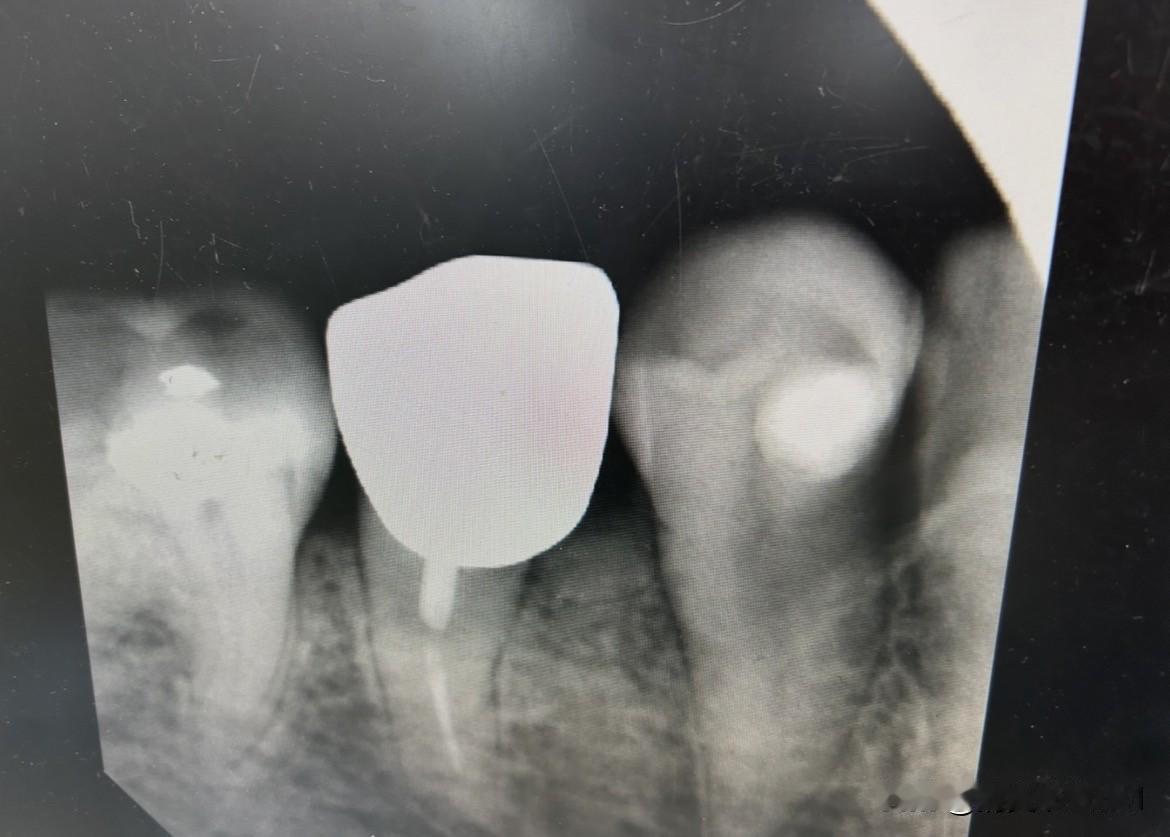

种牙和拔牙哪个更疼? 我的牙从补牙到打桩镶牙冠,再到桩子折牙冠脱落,历经8年,现在大夫让我拔牙然后种牙,我很怕疼。 拔牙犹豫了一个月,终于下决心下个月拔了吧,但还是纠结种牙或者义齿,但大夫说义齿要有挂钩在前后牙,会对它们产生伤害的。 不管怎么说也要拔牙三个月以后再决定吧。[捂脸]